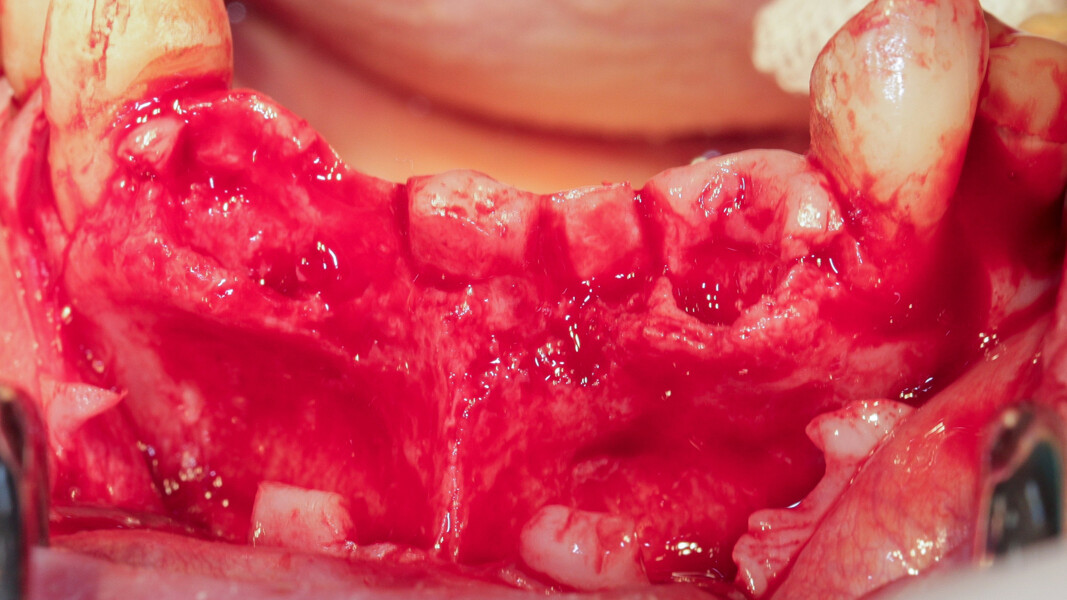

Pour se faire il a été décidé d’exploiter les racines extraites (11 et 21) pour reconstruire la paroi vestibulaire des alvéoles. Nous réalisons un lambeau avec une incision sulculaire de 13 à 23, en prenant soin de préserver les papilles interdentaires, ainsi que deux décharges verticales en distal des canines. Nous réalisons un décollement de pleine épaisseur (Fig. 11). Les dents sont facilement extraites et les alvéoles curetées avec soins. Deux implants (4*10) sont positionnés dans la paroi palatine des alvéoles, il subsiste une déhiscence vestibulaire (Fig. 12). La racine de 11 est séparée dans le sens de la longueur en deux fragments. Les racines préparées comme indiqué ci-dessus, sont vissées en vestibulaire de la crête au moyen de deux vis d’ostéosynthèse (diamètre 0,9 mm) afin de reconstruire la paroi vestibulaire (Figs. 13 et 14). L’espace entre l’implant et le greffon est comblé avec un matériau synthétique (Collapat II, SYMATESE). Le lambeau est tracté, suturé coronairement avec un fil tressé synthétique 5.0 (Fig. 15). Une empreinte est prise à la fin de l’intervention, le provisoire, préparé dans la journée par notre laboratoire de prothèse est vissé le soir même (Fig. 16). L’implant 21 ayant un couple de serrage insuffisant pour être mis en fonction, il s’agit d’un provisoire cantilever, direct implant, vissé sur l’implant 11 (Fig. 17).

Nous réalisons un lambeau avec une incision crestale décalée en palatin en 11 et 21, sulculaire en 12, 13, 22, 23, en prenant soin de préserver les papilles interdentaires, ainsi que deux décharges verticales en distal des canines. Nous réalisons un décollement de pleine épaisseur (Figs. 28 et 29). Les dents (12, 22 et 18) sont facilement extraites et les alvéoles curetées avec soins. Deux implants (4*13) sont positionnés dans la paroi palatine des alvéoles, il subsiste une déhiscence vestibulaire en 22. Les racines de 12, 22 et 18 sont séparées dans le sens de la longueur. Les racines préparées comme indiqué ci-dessus, sont vissées en vestibulaire et en occlusal de la crête, au moyen de vis d’ostéosynthèse (diamètre 0,9 mm), afin de reconstruire la crête osseuse au niveau des inters de bridge ainsi que la paroi vestibulaire de la crête au niveau de 22 (Figs. 30 et 31). Le gap vestibulaire entre les implants et la crête ainsi que l’espace entre la crête et le greffon au niveau de 21, sont comblés avec un matériau d’origine synthétique (Collapat II Symatese). Le lambeau est tracté, suturé coronairement avec un fil tressé synthétique 5.0 (Fig. 32). Des piliers coniques droits pour prothèse plurale transvissée sont posés, et une empreinte prise à la fin de l’intervention (Fig. 33). Un provisoire est réalisé dans la journée par notre laboratoire de prothèse et posé le soir même. (Figs. 34 et 35)